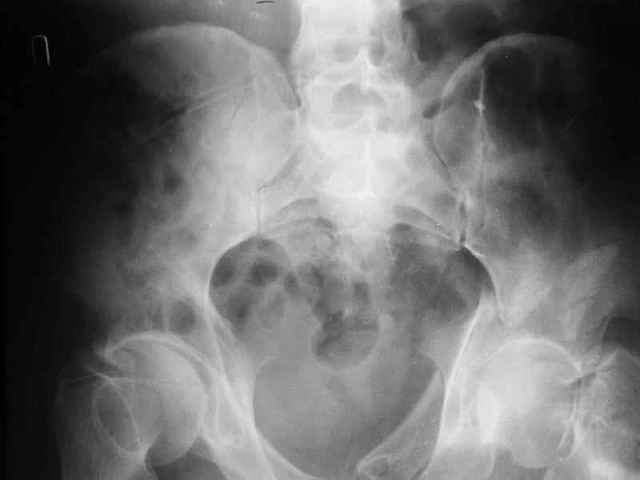

При поступлении в госпиталь 3.06.03

Больной 18 мая 2003 года в автоаварии получил перелом левой вертлужной впадины, вывих бедра. Госпитализирован в один из стационаров области.Вывих вправлен. В последствии бедро вывихивалось еще дважды. На консультацию был представлен снимок от 19.05.03г., больной переведен к нам 3.06.03г. Снимок при поступлении - перелом впадины, задне-верхний вывих бедра. 05.06.2003 г. выполнено открытое вправление вывиха левого бедра и остеосинтез стенки вертлужной впадины двумя винтами. Послеоперационный период без осложнений. Объем движений в левом тазобедренном суставе восстановился полностью. Выписан на амбулаторное лечение в удовлетворительном состоянии с рекомендациями 3 месяца ходить на костылях без нагрузки на оперированную конечность. На контрольных рентгенограммах левого тазобедренного сустава 13.10.2003 г. - признаки консолидации перелома; плотность, форма головки и состояние суставных поверхностей удовлетворительные. Разрешена дозированная осевая нагрузка, на конечность с использованием дополнительной опоры. 19.12.2003 г. больной обратился с жалобами на боли в левом тазобедренном суставе. На рентгенограммах левого тазобедренного сустава 19.12.2003 г., 20.02.04г. - асептичекий некроз головки бедра. 5.04.04г. - эндопротез. Сейчас ходит без трости, не хромает. Особенность эндопротезирования - при удалении винтов прослежена линия перелома заднего края впадины и предложено установить чашку несколько меньшего диаметра, чтобы она была покрыта несломанной частью.